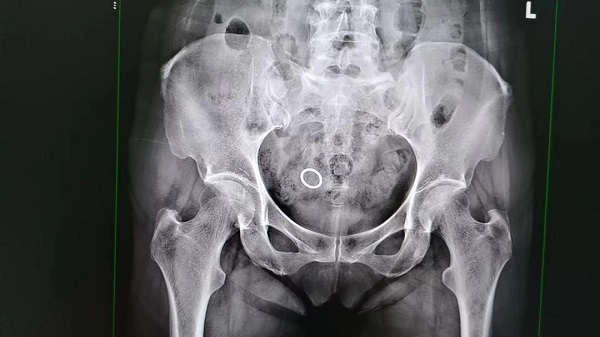

近日,62岁的汪阿姨来到复旦大学附属中山医院青浦分院妇科取环,术前B超提示环位宫体,X线显示盆腔一枚清清楚楚的金属圆环,可是宫腔镜下宫腔空空如也。那么这枚环,到底跑哪里了呢?为什么术前检查都能看见,而宫腔内的摄像头(宫腔镜)却看不见呢?

汪阿姨虽然术中经历了一点小插曲,但最后还是在超声科医生的帮助下,发现这枚“消失”的环,原来是嵌顿到了子宫后壁肌层里,妇科医生在宫腔镜下一点点剪开子宫后壁,终于见到了这枚“消失”的环,并顺利取出。